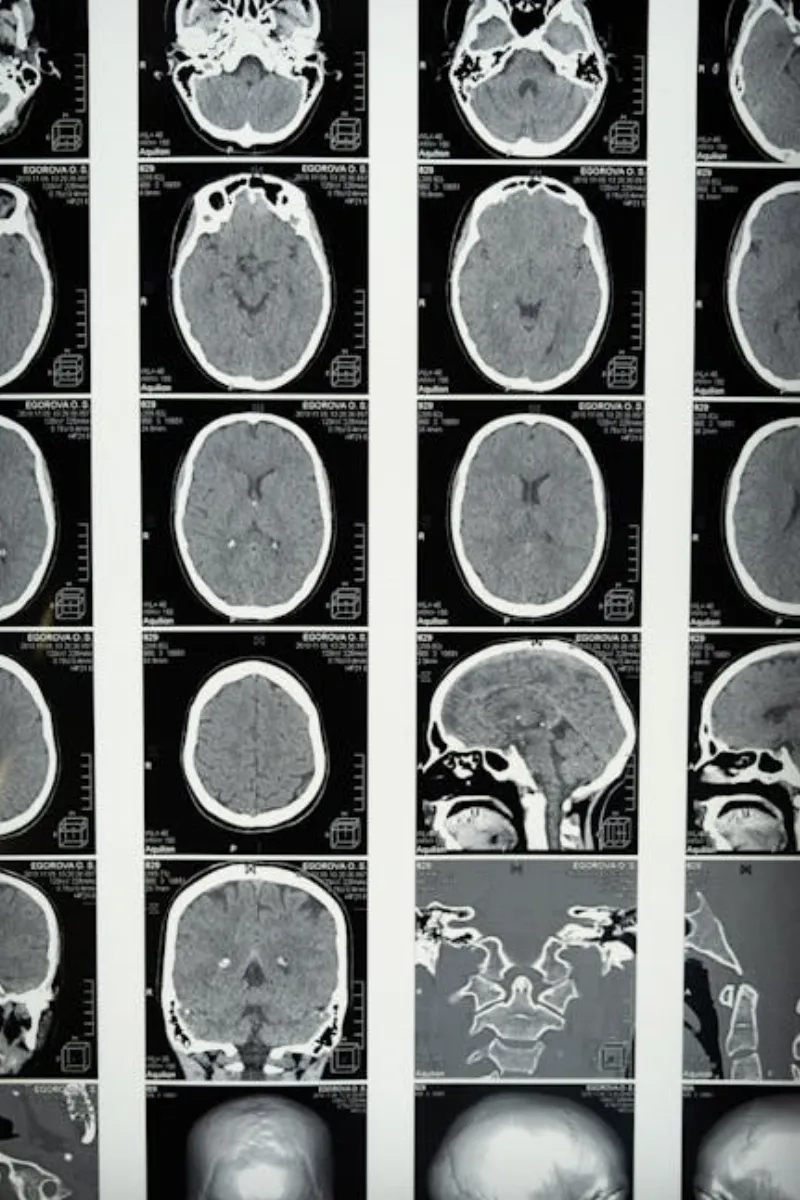

La Ciencia Detrás de la Actividad Cerebral

Según un estudio publicado en la revista Nature Communications, las exploraciones cerebrales muestran que los niveles de actividad se disparan durante las etapas iniciales del sueño. De hecho, ciertas áreas del cerebro involucradas en el procesamiento de emociones y recuerdos pueden volverse aún más activas cuando estamos dormidos. Es como si nuestros cerebros estuvieran trabajando horas extra, clasificando las experiencias del día y preparándonos para mañana.